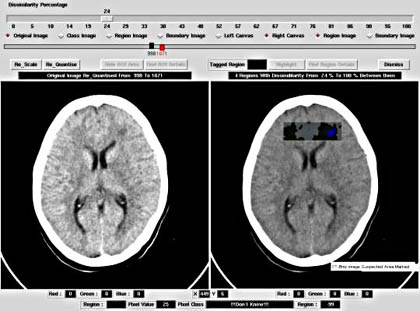

A software for automatically segmenting dissimilar regions in medical images acquired with magnetic resonance imaging, computed tomography or ultrasonography has been developed and implemented. The software can be used to highlight abnormal regions in medical images.

The algorithm operates in unsupervised mode hence does not require any parametrisation. This allows the physician to fully focus on the task of identifying diseased areas.

'The program has delineated the diseased area very clearly with a unique colour. The other part of the image with the same colour outside the diseased part of the image, can be differentiated by the physician as the non-diseased area as it is in the border of the uterus.

Looking at the original image only an expert sonologist will be able to pick up this abnormality. Therefore this program will be surely useful to differentiate in case of borderline pathology where the sonologist will not be very sure of the diseased area.

The separate region within the diseased area gives additional information that, that area has got the core of the disease, and it is spreading out from that location'

- comment from a sonologist